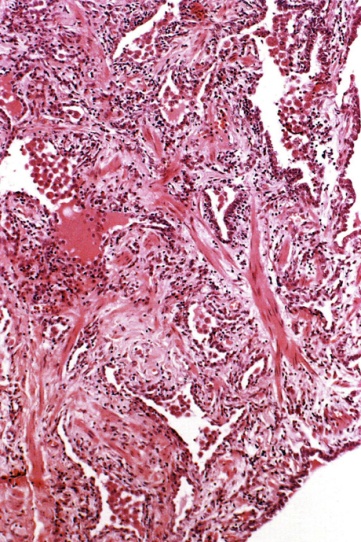

Plicní fibróza

Plicní fibróza.

Radiační fibróza plic, tj. zmnožení fibrózní plicní tkáně, je konečným stádiem postradiačních plicních změn. Radiační fibróza plic je syndromem, který se objevuje po ozáření plicní tkáně ionizujícím zářením až po 30 týdnech a jako u radiační pneumonitidy po dávkách větších než 8 Gy. Ionizujícím zářením způsobené nekrotické změny jsou hojeny fibrotickou jizvou. Avšak proces hojení u ozářených tkání není stejný jako u konvenčních poranění, nýbrž je aktivován i několik let a fibrotické jizvy reprezentují nepravidelně uspořádaná kolagenní vlákna.